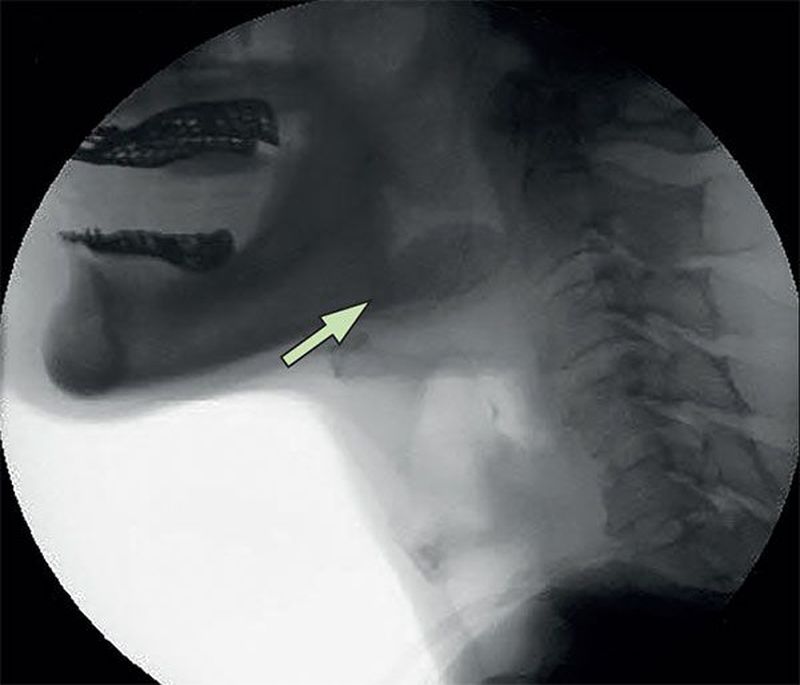

A 49-year-old man presented with gradual onset of dysphagia with aspiration symptoms. The neck CT showed a giant cyst on the lingual surface of the epiglottis. Which of the following tests would be considered the gold-standard method of investigating this patient’s problem? A)Ultrasound B)MRI of the neck C)Videofluoroscopic swallowing study D)Gastrofiberscopy